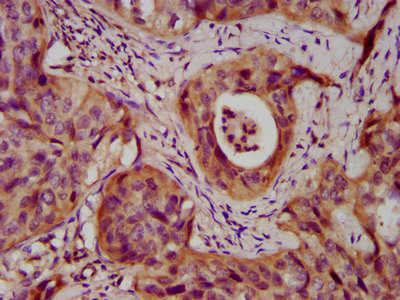

IHC image of CSB-PA613507LA01HU diluted at 1:400 and staining in paraffin-embedded human prostate cancer performed on a Leica BondTM system. After dewaxing and hydration, antigen retrieval was mediated by high pressure in a citrate buffer (pH 6.0). Section was blocked with 10% normal goat serum 30min at RT. Then primary antibody (1% BSA) was incubated at 4°C overnight. The primary is detected by a biotinylated secondary antibody and visualized using an HRP conjugated SP system.